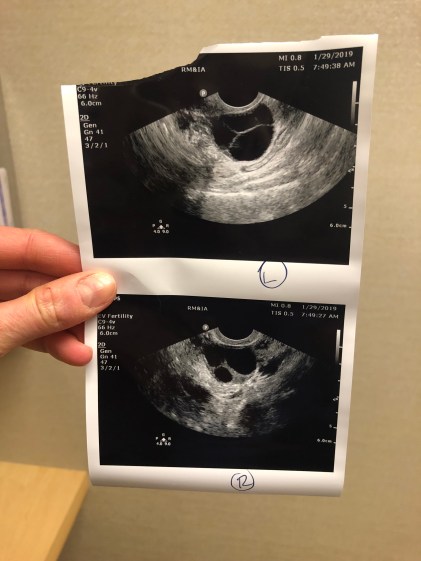

IMG_6029

The ultrasound images are of my Left ovary (top) and my Right ovary (bottom).  The big black circles are some of the follicles!